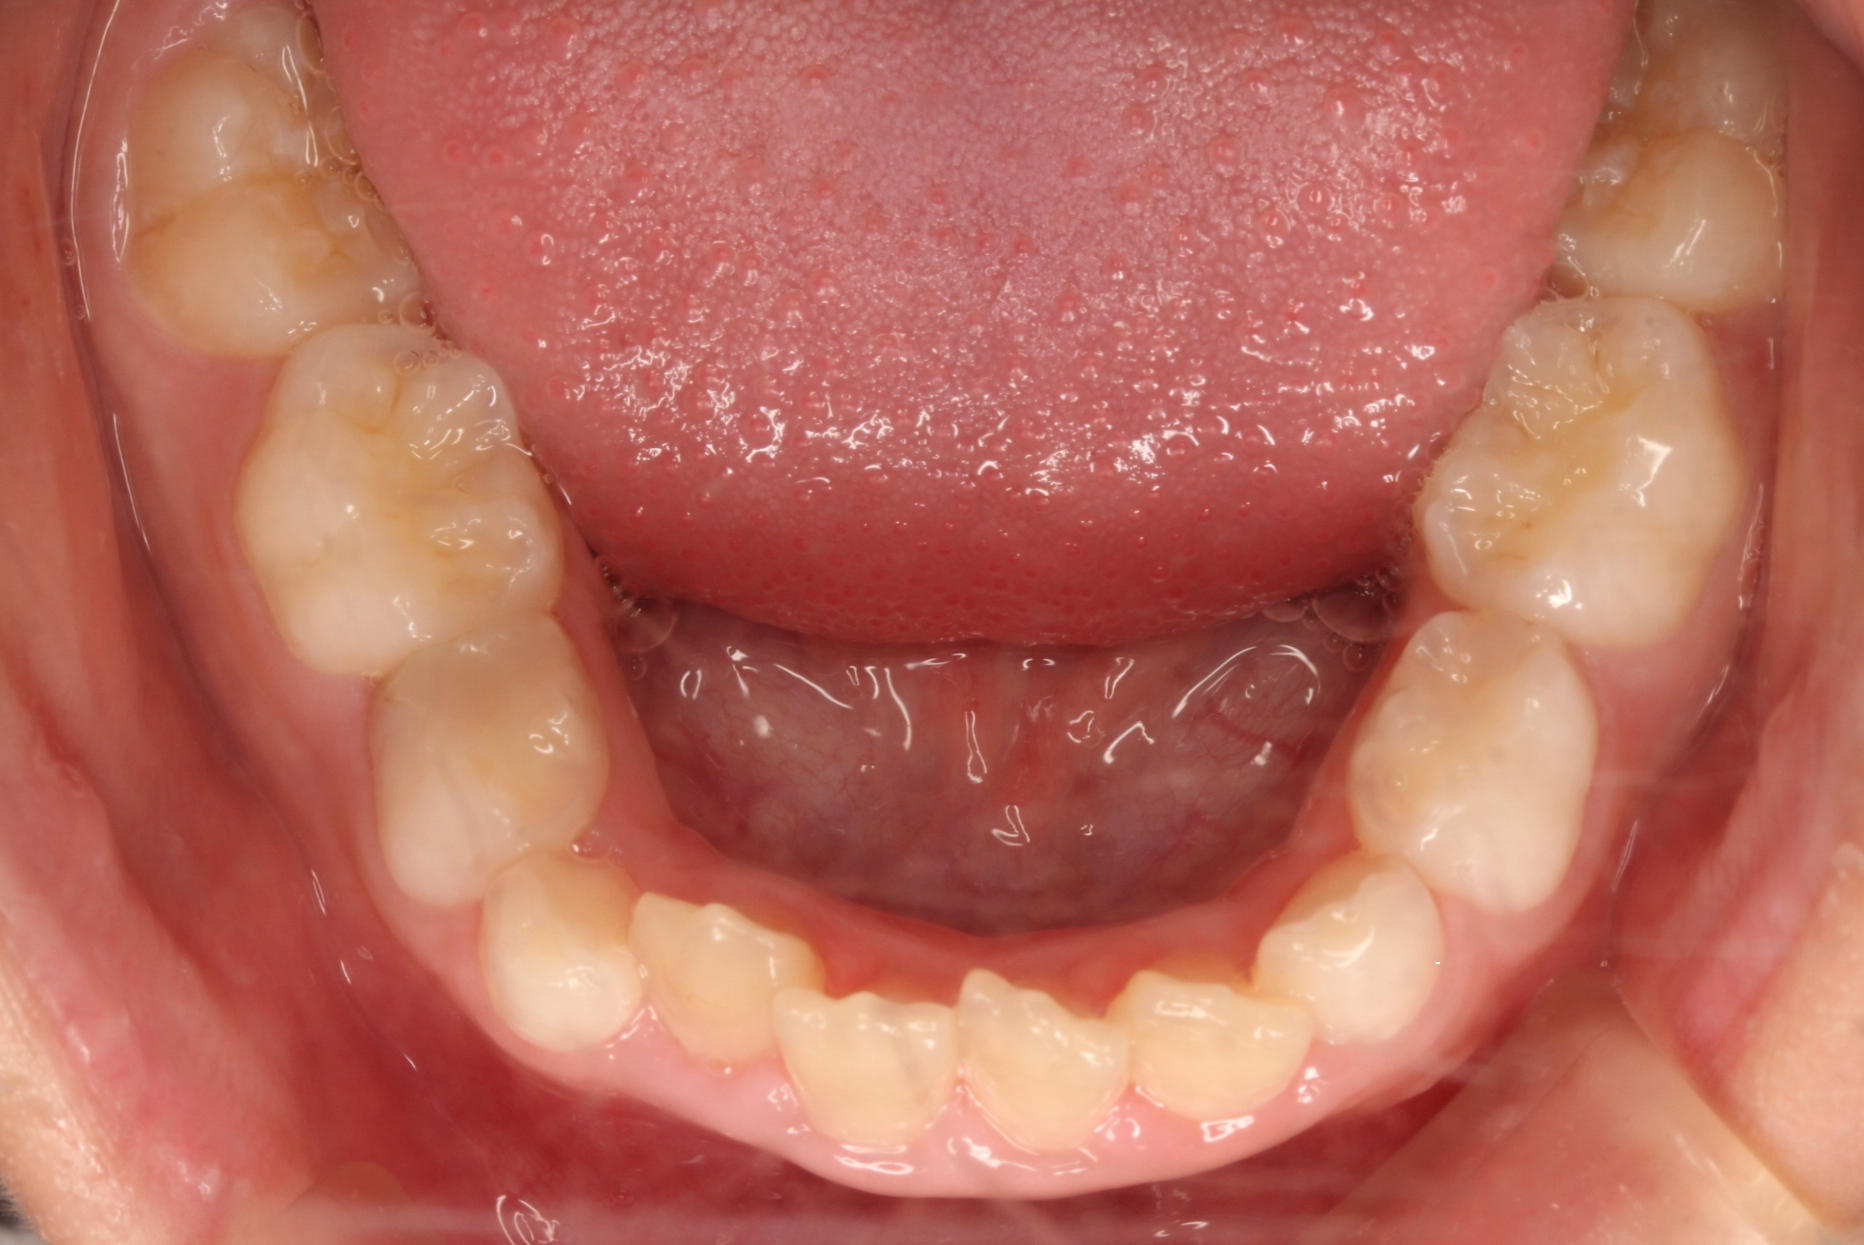

矯正術前:下顎

矯正術後:下顎